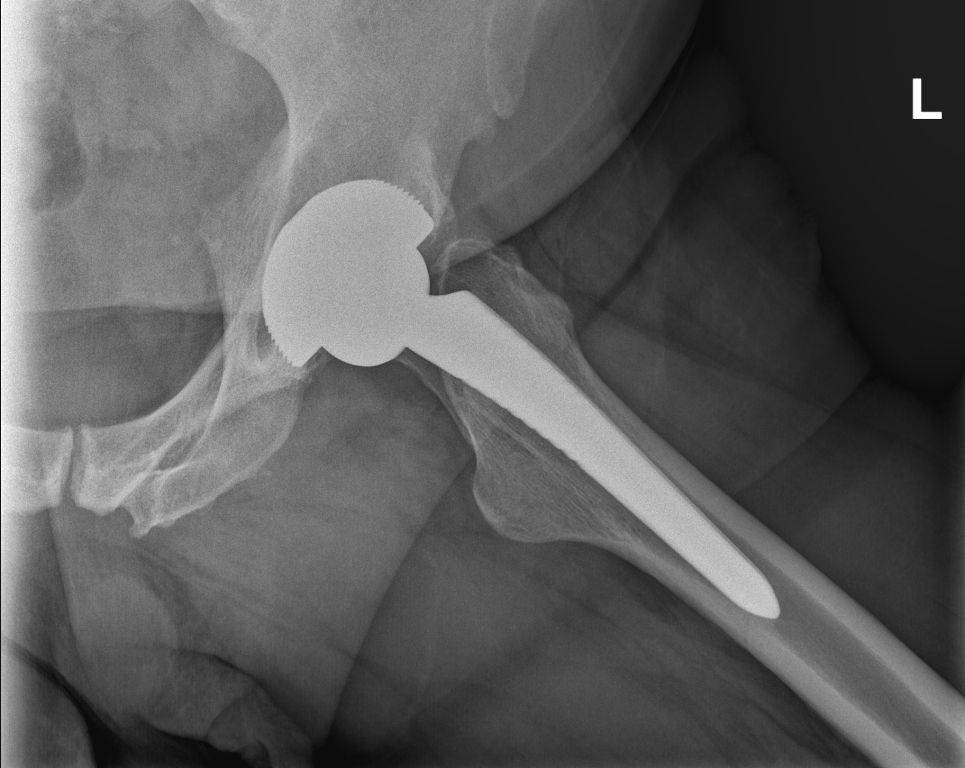

Meine Frage, ob ich meine Prothese sehen könnte, wurde aus Sterilitätsgründen verneint, aber ich habe mich recht gut vorbereitet, daher kann ich hier auch ein Referenzbild zeigen. Die eigene wäre aber trotzdem interessant gewesen.

Bei fachgerechter Operation (siehe dazu das Kapitel am Ende) beträgt die Lebensdauer der Hüft-TEP (Totalendoprothese des Hüftgelenks) heute 20 bis 25 Jahre, oft sogar länger. Offiziell werden trotzdem 15 Jahre kommuniziert, ich habe aber mit einigen Leuten gesprochen, die ihre Endoprothese ohne Probleme schon länger als 20 Jahre haben.